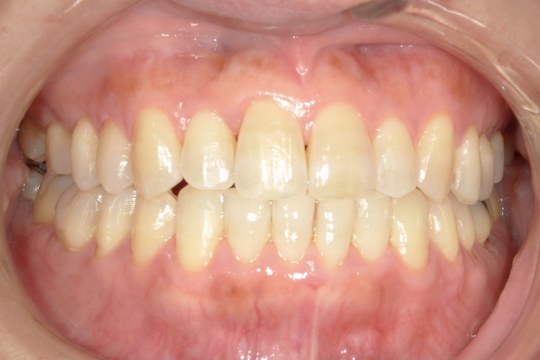

Y.S. 30代男性

全体的にガタガタしているのが気になるという主訴だったため、上下左右第一小臼歯を抜歯し、叢生を並べました。

治療の期間:R3. 9/1〜R5. 10/31

治療の価格:88万円